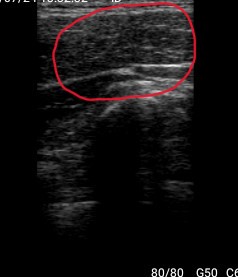

②エコー検査

徒手検査だけでは捉えきれない内部構造を可視化し、正確に状態把握と判断を支援します。

筋肉の動きや炎症所見をリアルタイムに確認することで、施術の精度を高めます。

←施術前:白い靄が多く、筋肉同士が癒着し

滑走が悪い状態